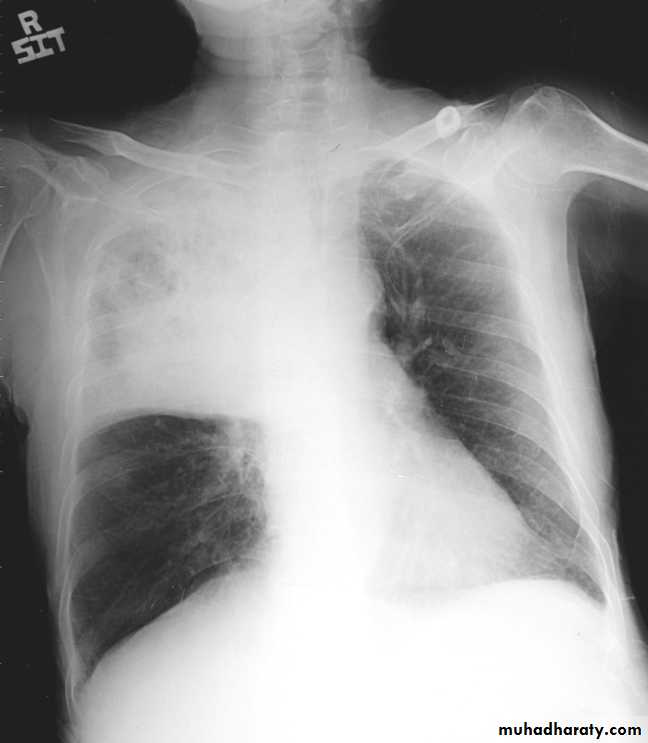

48.opasified hemi thorax Total collapse

Homogenus opacity of the right hemithorax with shifting of the trachea to the same side48.opasified hemi thorax Total consolidation

Homogenus opacity of the left hemithorax with central trachea

Total collapse

Homogenus opacity of the left hemithorax with shifting of the trachea to the same sidePleural effusion